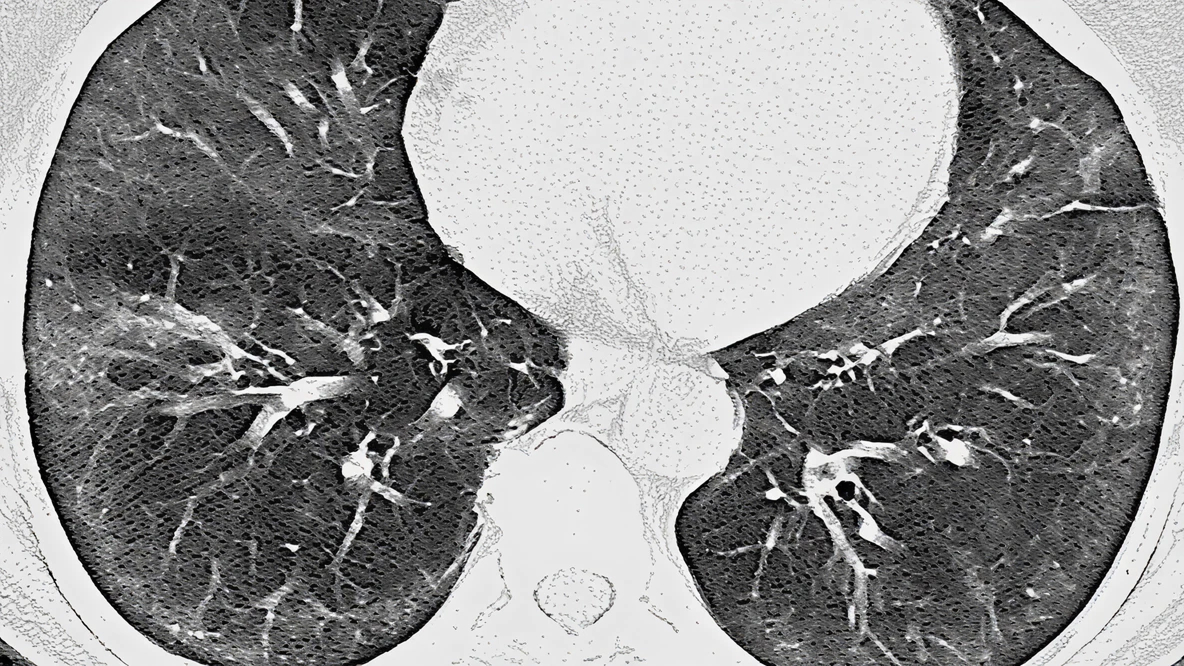

IPF – OBRAZ UIP

IPF - obraz UIP

Wytyczne ATS/ERS/JRS/ALAT zalecają pewne rozpoznanie IPF, jeśli ocena kliniczna pacjenta wskazuje na IPF, a badanie HRCT wykazuje definitywny lub prawdopodobny obraz UIP (zalecana biopsja warunkowa).2

Dlaczego wczesne badania przesiewowe i rozpoznanie IPF w badaniu HRCT są tak ważne?